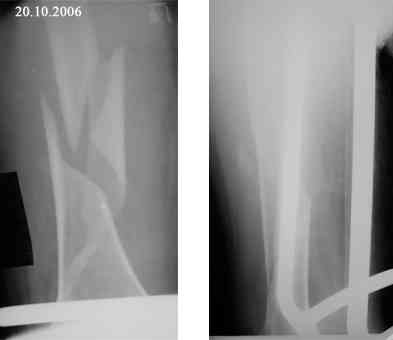

В продолжение темы оскольчатого перелома бедренной кости.

Р-граммы в динамике